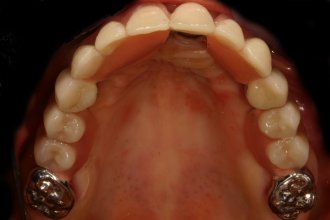

Ein preiswerter Ersatz für Teleskope im hinteren Backenzahnbereich sind Ankerbandklammern. Sie können stützen und haben Haltekraft. Sie sind aber nicht so präzise gearbeitet, wie ein Teleskop und immer unverblendet. In diesem Fall wurden zwei Implantate gesetzt. Wir haben dadurch eine optimale Pfeilerverteilung und konnten eine brückenartige Konstruktion herstellen.